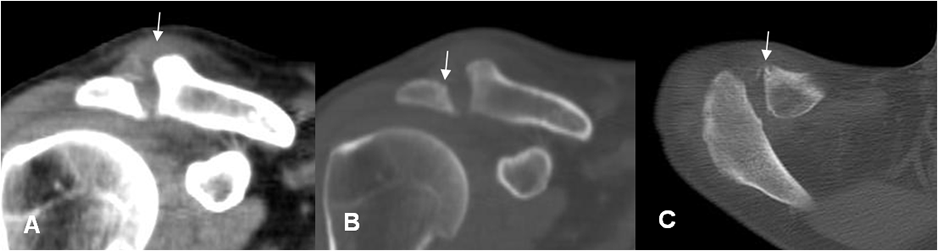

En la fase aguda la Rx simple puede ser normal. También puede existir edema de tejidos blandos y derrame articular. En niños el estudio comparativo es de mucha utilidad. (16). (Fig 63 A, 63 B y 63 C).

Fig 63 A. Artritis séptica.

A: Rx lateral. Artritis infecciosa, como complicación de la reducción abierta, de una fractura de patela.

B: Ecografía, donde se confirma la presencia de derrame articular.

Fig 63 B. Artritis infecciosa.

A: TAC reconstrucción coronal. Aumento del espacio acromioclavicular, con prominencia en los tejidos blandos en la parte superior.

B: TAC reconstrucción coronal y C: TAC axial. Incipientes esrosiones óseas en la clavícula y el acromión, por artritis infecciosa.

Fig 63 C. Artritis séptica.

A: Rx pelvis AP. Desplazamiento del cojinete graso de la cadera, como signo de derrame articular. (Comparar con el contralateral).

B: RM coronal en STIR. Derrame articular, de donde se cultivó estafilococo aureus.